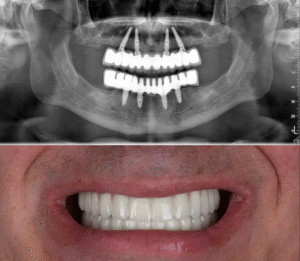

All-on-6 zubni implantati – prednosti i moguće mane

април 2, 2025

All-on-4 zubni implantati – prednosti i moguće mane